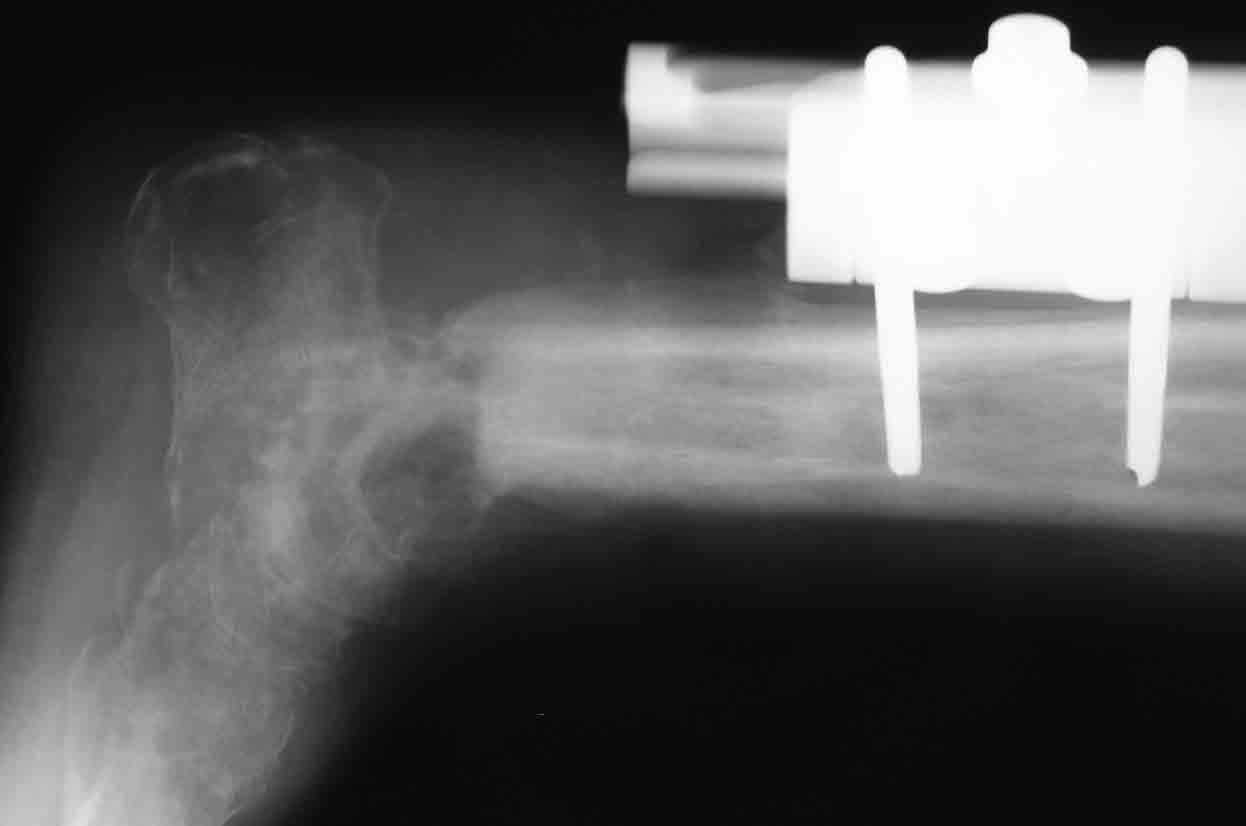

下图  X线片显示,左胫骨延长区骨质稀疏,透光度高,延长截骨平面在关节面下5厘米。

1、不能做膝下平面截肢手术。因为左胫骨延长截骨平面在关节面下5厘米,标准的膝下截肢平面应当是在关节面下15厘米,截肢平面恰好为延长区,延长区骨质稀疏松软。如果在此平面截肢,术后负重时很可能延长区新骨不堪重负塌陷,需要重新截肢修整。患者要求保留膝关节,如果再次向近端截肢,膝关节面下有强度的胫骨只能保留5厘米,无法安装小腿假肢。如果做膝上截肢,患者不接受,那时就有麻烦了,进退两难。